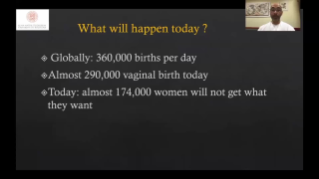

WomenŌĆÖs health is the foundation of health for all and is especially important for countries with aging populations and low fertility levels. MindrayŌĆÖs solution protects multiple life stages, including reproduction, prenatal and intrapartum, and postpartum pelvic floor, with accurate images and efficient and easy-to-use intelligent applications to help caring womenŌĆÖs health in all aspects and cycles.